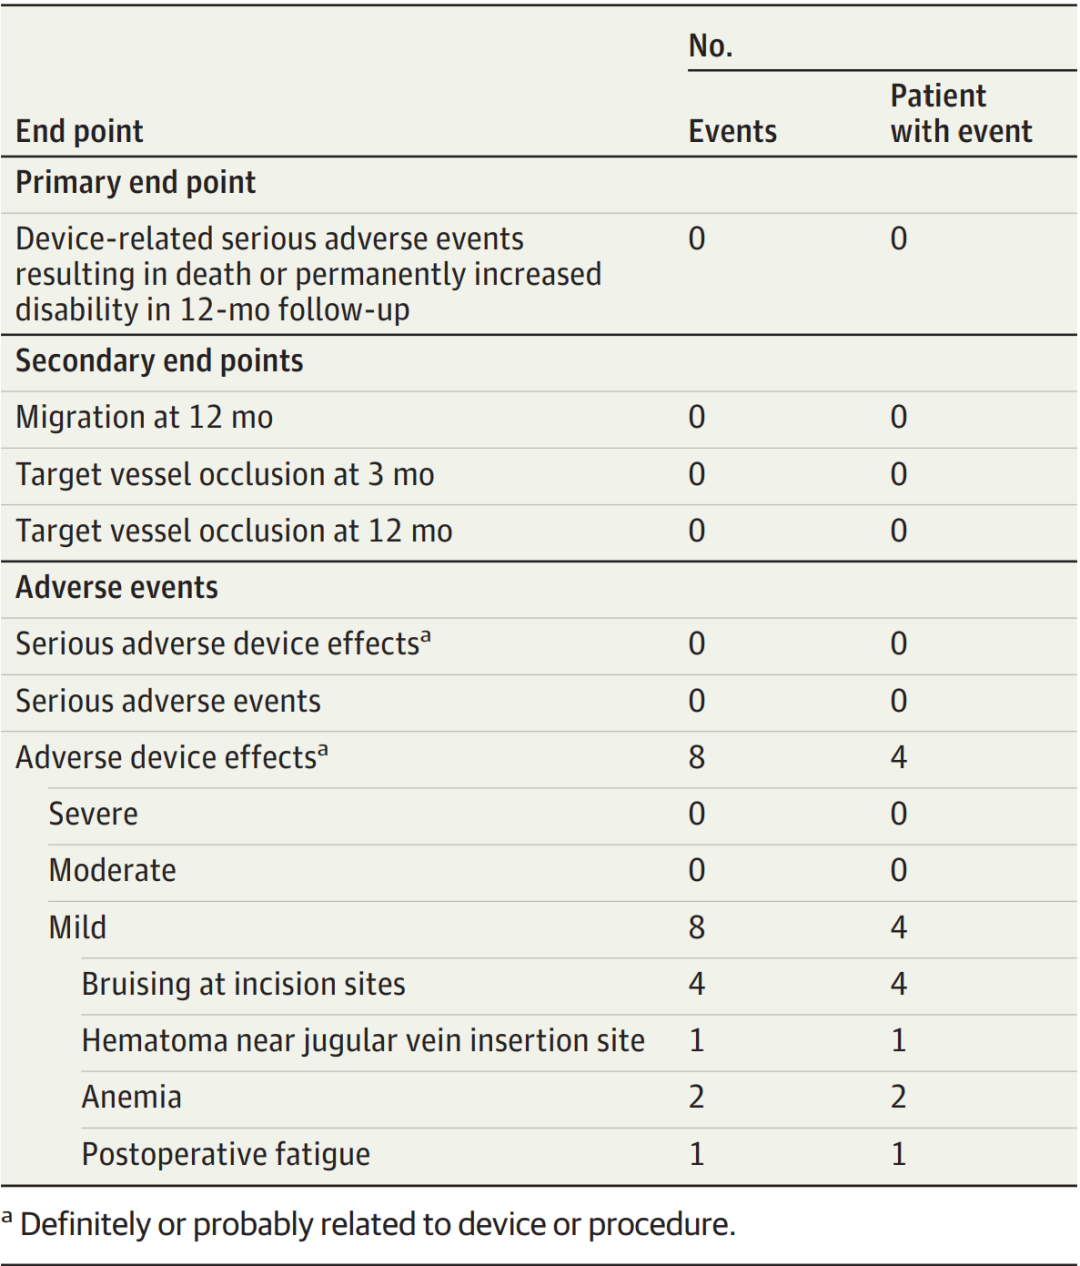

主要终止节点是植入后12个月内导致死亡或永久性残疾的与设备相关的严重不良事件。

次要终止节点为目标血管闭塞和设备迁移,由独立的血管神经科专家根据植入前、植入后3个月和12个月的CT静脉造影进行评估。

在主要终止节点评估中,在植入术和12个月随访期间,没有发生导致死亡或永久性残疾的器械相关严重不良事件。研究期间未发生严重的器械不良反应或不相关的严重不良事件。有8例不良器械反应,这些不良反应被归类为轻度,无需干预即可解决(表2;不严重的事件包括头痛和切口部位的瘀伤。对于次要终止节点,回顾3个月和12个月的CT静脉造影,4例患者均未发现目标血管闭塞或血栓形成。在3个月和12个月的静脉造影中,远端电极与基准线之间距离的值为0.45±0.28mm,表明装置位置在临床上没有显著变化(图2)。

表2.安全性终止节点